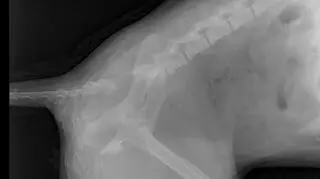

- Ma w dwóch miejscach złamany kręgosłup. Trzeba było podjąć decyzję o leczeniu, bądź eutanazji. Przeszła operację. Szanse na to, że kiedyś stanie na łapy są niemal zerowe, ale da sobie radę przy pomocy wózka - mówi Pisarska.